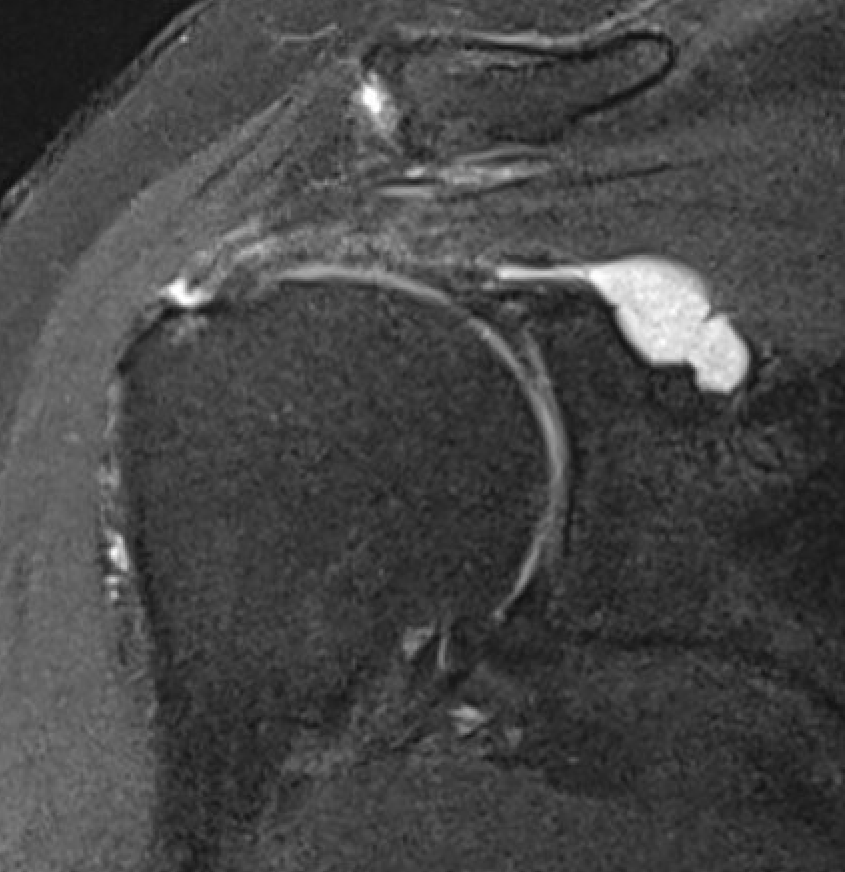

Spinoglenoid Cyst

MRI

Spinoglenoid cyst with SLAP tear and posterosuperior labral tear